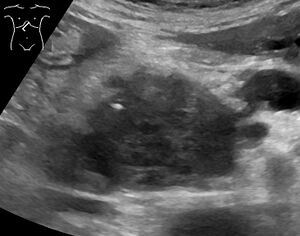

تُستخدم تقنيات التصوير الطبي، مثل التصوير المقطعي المحوسب والتنظير بالموجات فوق الصوتية لتأكيد التشخيص وللمساعدة في تحديد ما إذا كان يمكن إزالة الورم جراحيًا ("قابلية الاستئصال").[12] في تباين التصوير الطبقي المحوسب، يظهر سرطان البنكرياس عادةً زيادة تدريجية في امتصاص الأشعة، بدلاً من الانجراف السريع كما يظهر في البنكرياس الطبيعي أو الاغتسال المتأخر كما يظهر في التهاب البنكرياس المزمن.[29] يمكن أيضًا استخدام التصوير بالرنين المغناطيسي والتصوير المقطعي بالإصدار البوزيتروني،[2] وقد يكون تصوير الپنكرياس والقنوات الصفراوية بالرنين المغناطيسي مفيدًا في بعض الحالات.[22] الموجات فوق الصوتية على البطن أقل حساسية ولا تظهر الأورام الصغيرة، ولكن يمكنها تحديد السرطانات التي انتشرت في الكبد وتراكم السوائل في التجويف البريتوني (الاستسقاء).[12] يمكن استخدامها لإجراء فحص أولي سريع ورخيص قبل التقنيات الأخرى.[30]